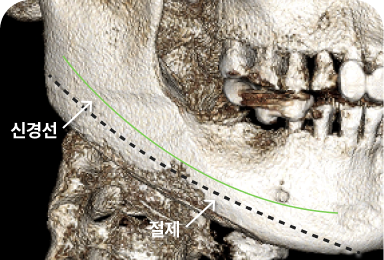

신경 보존 절골법

• 신경 보존 절골법 이미지

무분별한 절골은 감각 이상과 같은

심각한 후유증을 남길 수 있습니다

신경 손상을 최소화하여

안전을 최우선으로 합니다

수술 전 3D-CT를 통해 신경의 위치를

1mm까지 분석하고,

원장님이 직접 수술 경로를 디자인하여

신경 손상을 원천 차단합니다

* 수술전 원장님이 직접 디자인한 사진입니다